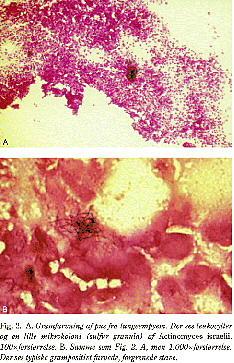

Mikroskopi: grampositiv, forgrenet bakterie (Fig. 2. A). Biopsi fra granulationsvævet viser en ydre zone af granulationsvæv og et centralt purulent materiale med neutrofile leukocytter, lymfocytter og plasmaceller omgivet af svovl-granula, der består af konglomerater af mikroorganismen (Fig. 2. B). Ofte kan der findes mange granula. Actinomyces skal dyrkes anaerobt i mindst fem dage.